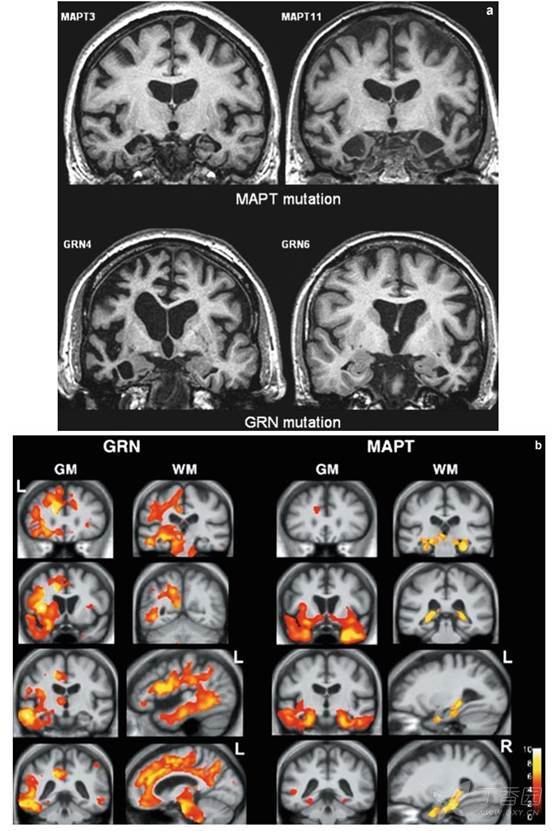

看图说话:路易体痴呆,额颞叶变性及正常压力脑积水的影像学特征丨实战